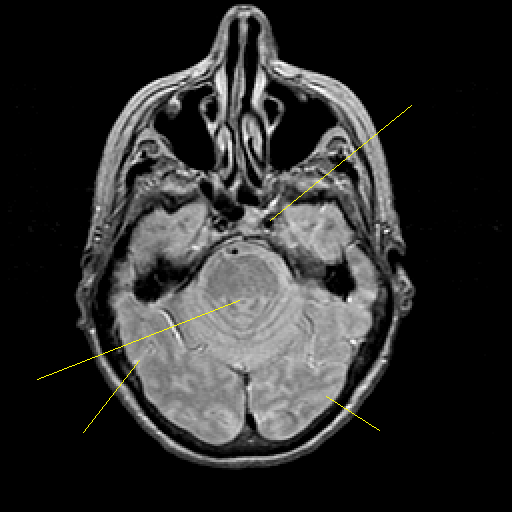

Proton density-weighted structural MR: Slice 16

Slice 16

Pointers

Labeled